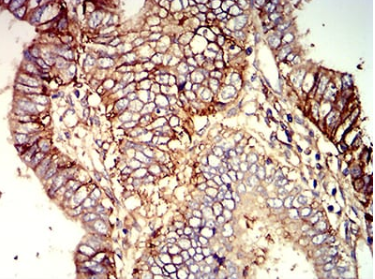

B7H3 Mouse Monoclonal antibody[8C1C2]

The protein encoded by this gene belongs to the immunoglobulin superfamily, and thought to participate in the regulation of T-cell-mediated immune response. Studies show that while the transcript of this gene is ubiquitously expressed in normal tissues and solid tumors, the protein is preferentially expressed only in tumor tissues. Additionally, it was observed that the 3' UTR of this transcript contains a target site for miR29 microRNA, and there is an inverse correlation between the expression of this protein and miR29 levels, suggesting regulation of expression of this gene product by miR29. Alternatively spliced transcript variants encoding different isoforms have been found for this gene.

IHC    1/200 - 1/1000